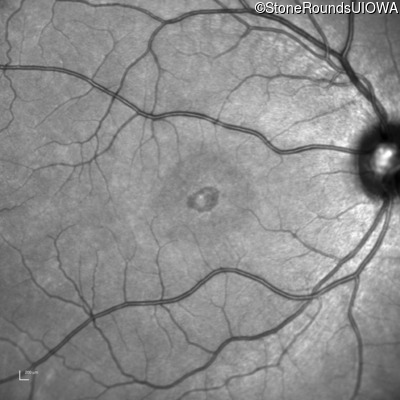

Age at visit: 16 years

Age at visit: 17 years

Age at visit: 18 years

Age at visit: 22 years